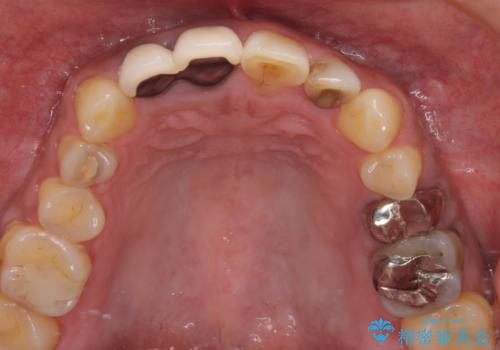

前歯の審美歯科治療 下顎の部分矯正と上顎前歯のオールセラミッククラウン

- 前歯の見た目を気にして来院された患者様です。

部分矯正をしたくて下顎前歯に矯正装置を付けていらっしゃいましたが、通院が難しいこともあり撤去することになりました。

下顎の歯列は整えたいというご希望とは別に、上顎前歯にうずくような痛みや違和感があるとのことで、先に根管治療や歯根端切除術を行うこととしました。

痛みが消えた後に、より目立たない装置をご希望とのことで、下顎前歯の舌側矯正で部分矯正を行い、歯列が整い、上顎前歯歯根部の病変が消退したことを確認した上で、上顎前歯をオールセラミッククラウンにて補綴治療を行うこととしました。